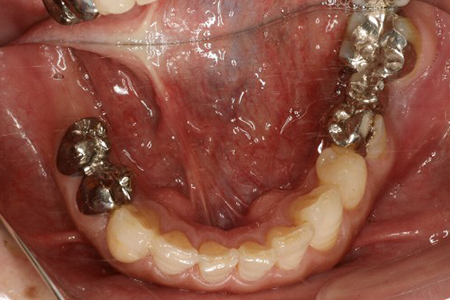

下顎の症例 埋入用ステント

- 術前

- 術中

- 術後

- 埋入位置の表示

インプラントが5本埋入 治癒期間1年半 費用 450万(税別)

術後8年

現在メインテナンス中で経過良好です

リスク・副作用としてインプラント周囲炎があります